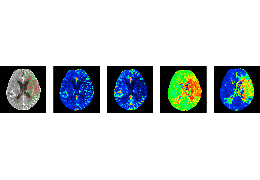

ART-Plan™ Artificial Intelligence Contouring